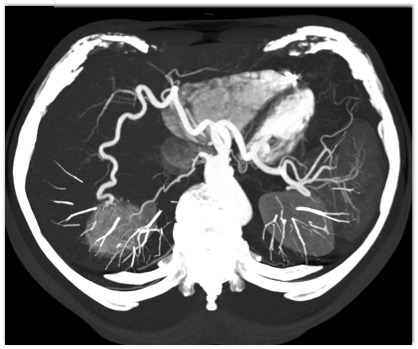

The least likely diagnosis in this case is?

focal nodular hyperplasia

hepatic adenoma

hemangioma

hydatid cyst